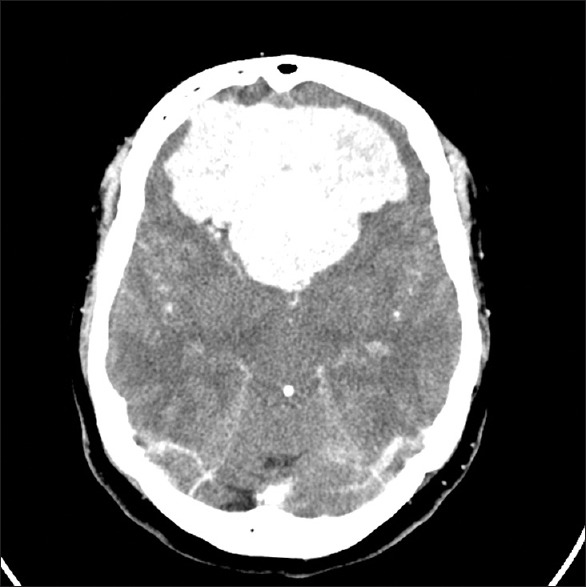

• 腦膜瘤的典型CT表現(xiàn)是什么?腦膜瘤MRI表現(xiàn)有哪些?

腦膜瘤的典型CT表現(xiàn)是什么?腦膜瘤MRI表現(xiàn)有哪些?

2021-08-04 10:48:50

腦膜瘤生長(zhǎng)緩慢,常壓迫周圍組織引起相應(yīng)的神經(jīng)癥狀和體征,造成不同的障礙與腫瘤部位有關(guān)。腦膜瘤的典型CT表現(xiàn)是什么?腦膜瘤MRI表現(xiàn)有哪些?...